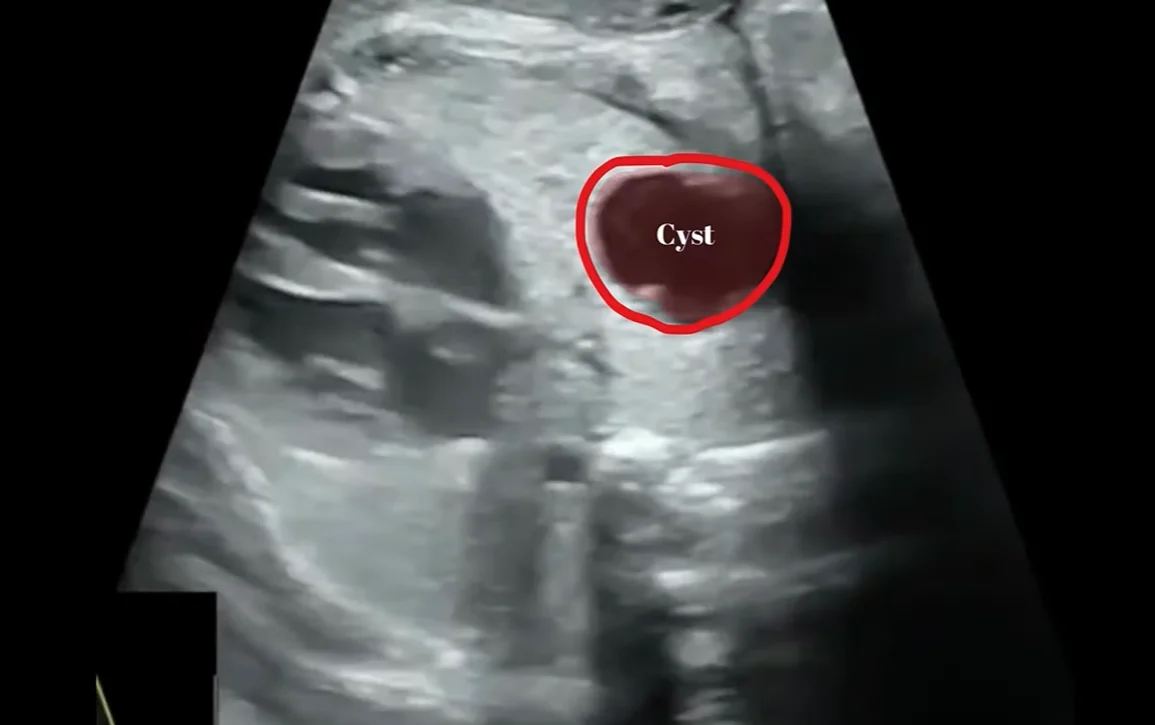

• Nang trong ổ bụng thai quý I

• Nang ổ bụng thai nhi (Cystic Abdominal Mass)